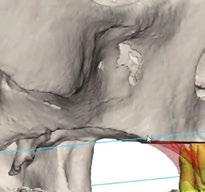

dentarias, cumpliendo parámetros biológicos, terapéuticos, mecánicos y estéticos. Después se realizó un modelado digital retrospectivo (Figuras 7-11) para generar modelos impresos 3D para realizar el mock up funcional, estético y como guía para las preparaciones (Figuras 12-15). Con ello, se efectuaron las preparaciones dentarias y los registros intermaxilares y, posteriormente, se digitalizaron ambos maxilares (Figuras 16-21)

En las piezas 16 y 17 el paciente presentaba restauraciones atornilladas de metalcerámica sobre implantes oseointegrados. Se planificó realizar estas en una fase posterior a la rehabilitación de las piezas dentarias mediante flujo digital con bases de titanio y cuerpos de escaneo.

Terminada esta fase se elaboró una propuesta de diseño (CEREC,

SW 5.2, Dentsply Sirona) (Figuras 22-27), la cual fue materializada en dos tipos de materiales a partir de bloques cerámicos IPS Empress CAD y cerámica vítrea de disilicato de litio IPS E.max CAD (Figuras 28-30)